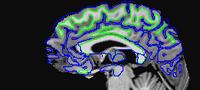

EPI images are significantly distorted relative to true brain anatomy. This is a problem because activation maps created from EPI images are overlaid on T1 images (or cortical surface models created from T1 images) which reflect the true anatomy. The following images show a T1 image with outlines for the outer boundary of gray matter (blue line) and white matter (green line).

Here are uncorrected EPI images with the same boundaries overlaid.